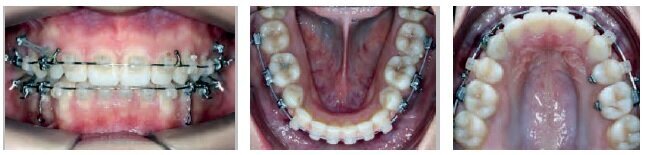

VISIT NO 5: 21 MONTHS

Seven months later, the family returned to the office over the summer break.

A long appointment was scheduled to—if all went well—remove the appliances and put a retainer in place. The day of the visit, the decision was made to proceed.

When I announced that the treatment would be completed that day, the patient and his parents had quite a memorable reaction: “Already? It went so fast! Thank you! He is going to have the best summer break!”

The results, although not perfect, were remarkable. The end-of-treatment records clearly show good tissue quality (periodontal and root integrity), undoubtedly thanks to the use of minimal force with long rest periods, a minimal number of archwires, and bonding which allowed for continuous improvement throughout the entire treatment, from beginning to end.